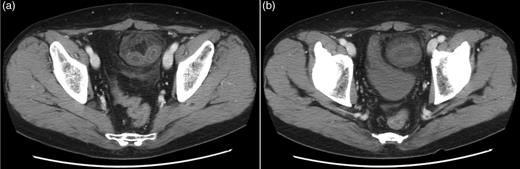

A 61-year-old Japanese man presented with an irreducible lump over his left groin, leading to the reduction of an incarcerated inguinal hernia by a doctor at another hospital. Later, he was admitted to our hospital with vomiting and abdominal pain. A physical examination revealed a soft abdomen, with some distension. Some tenderness was also noted over the lower abdomen, but there was no longer a lump over his left groin. CT showed a ball-like lesion containing an incarcerated bowel loop over his left pelvis (Fig. 1a and b). The patient was diagnosed with an incarcerated small bowel obstruction due to an inguinal hernia reduction en masse; a laparoscopic TAPP hernioplasty was performed.

(a) Contrast axial CT shows a closed bowel loop with surrounding preperitoneal fat. (b) CT scans at the inguinal levels show the hernia sac and its contents compressing the urinary bladder, so that it shows a beak-like deformity.

CT and an accurate clinical history are useful for making an accurate preoperative diagnosis. Kitami et al. [3] reported the CT findings of reduction en masse to include (i) a closed-loop obstruction with a ball-like bowel loop, (ii) a location adjacent to the inguinal fossa, (iii) a circular funicular structure at the obstruction point, (iv) a beak of the bladder along the closed loop and (v) a prominent unilateral inguinal soft tissue. Because a reduction en masse involves continued incarceration, prolonging the time to surgery increases the risk of complications and may be fatal. In our case, the characteristic CT findings were observed, allowing easy diagnosis of a reduction en masse and facilitating immediate corrective surgery.